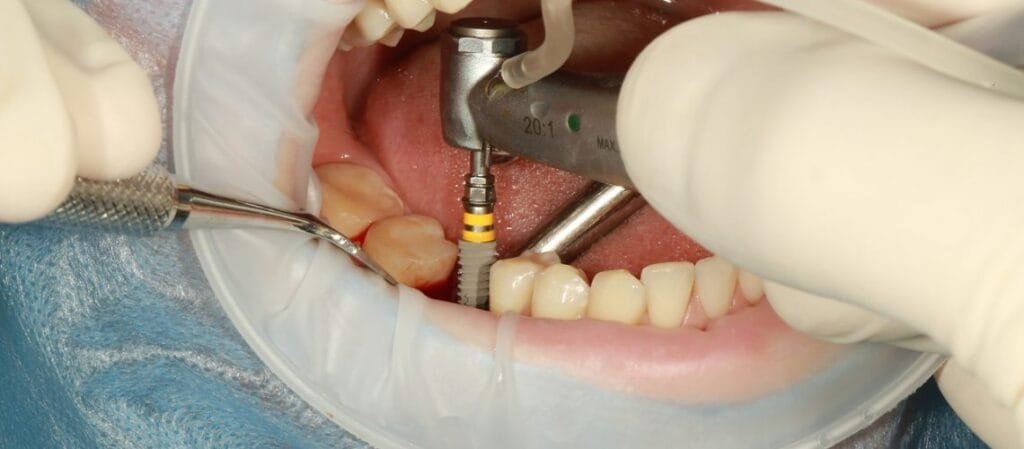

একটি আত্মবিশ্বাসপূর্ণ হাসি আপনার জীবন বদলে দিতে পারে। কিন্তু যদি দাঁতের অভাব আপনাকে পিছনে টানে? তাহলে, ডেন্টাল ইমপ্ল্যান্ট এর মাধ্যমে আপনার হারিয়ে যাওয়া হাসিকে ফিরে পান। ডেন্টাল ইমপ্লান্ট হল একটি স্থায়ী এবং প্রাকৃতিক সমাধান যা হারিয়ে যাওয়া দাঁত প্রতিস্থাপনের জন্য ব্যবহৃত হয়। ডাঃ অনুরাধা বোস ডেন্টাল ক্লিনিকে, আমরা আপনাকে আরামদায়ক,দীর্ঘস্থায়ীএবং উন্নত ডেন্টাল ইমপ্লান্ট চিকিৎসা প্রদান […]